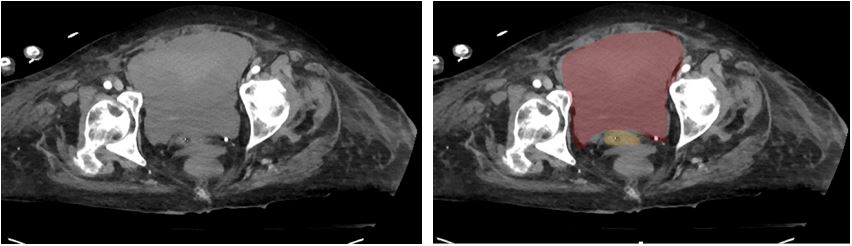

A 78-year-old female with a past medical history of recent CAD with NSTEMI and rectus sheath hematoma presented with severe abdominal pain via EMS. In transport, the highest heart rate was 35, and the lowest blood pressure was 93mmHg systolic. The patient had been discharged from rehabilitation four days prior to presentation. She reported mild pain at discharge that acutely worsened on the day of presentation. While the patient was being volume resuscitated, a RUSH exam was performed that showed severely reduced LVEF and a distended bladder. A foley was placed and minimal urine came out. The patient’s blood pressure and heart rate improved, and she was transported to the CT scanner, where a large pelvic hematoma was identified. The patient was taken for ex-lap and admitted to the surgical ICU.

Figure 3. Bladder Ultrasound. Red: Hematoma; Pink: Uterus

Figure 4. CT Abdomen and Pelvis. Red: Hematoma; Yellow: Bladder